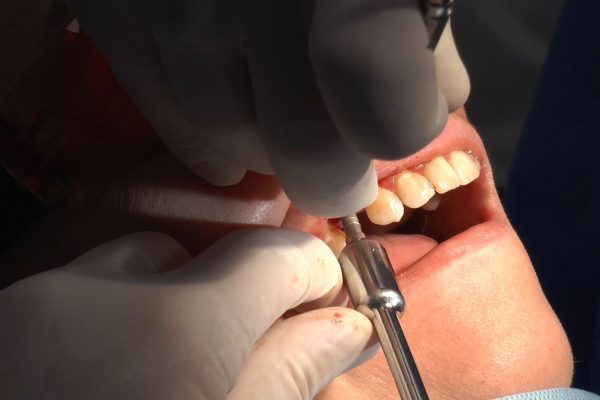

W ostatni weekend czerwca 2018 roku kursanci II Sezonu Preludium Implantologii odbyli piątą, finałową sesję, która w całości podporządkowana była praktyce. W ciągu dwóch dni zabiegowych Lekarze uczestniczący w szkoleniu przeprowadzili szereg zabiegów pod kierunkiem dr n.med. Violetty Szycik. Wszczepili 17 implantów oraz przeprowadzili ekstrakcje i zabiegi regeneracyjne kości. Zabiegi były wykonywane także w sedacji dożylnej z udziałem specjalisty anestezjologii i intensywnej terapii dr Jolanty Grzybowskiej. Preludium implantologii to nowy program edukacyjny dla adeptów implantologii stomatologicznej, którego celem jest wprowadzenie do implantologii poprzez pozyskanie wiedzy w szerokim zakresie i uwzględnieniem szczegółów mających decydujące znaczenie dla powodzenia leczenia implantologicznego. Ale tak jak wszystkie szkolenia w Instytucie Vivadental, w tym wiodące Practiculum Implantologii, zorientowane jest na praktyce i samodzielnym wykonywaniu zabiegów pod kierunkiem Mentora. To najlepsza edukacja w medycynie zabiegowej, a zarazem najlepszy start do implantologii.